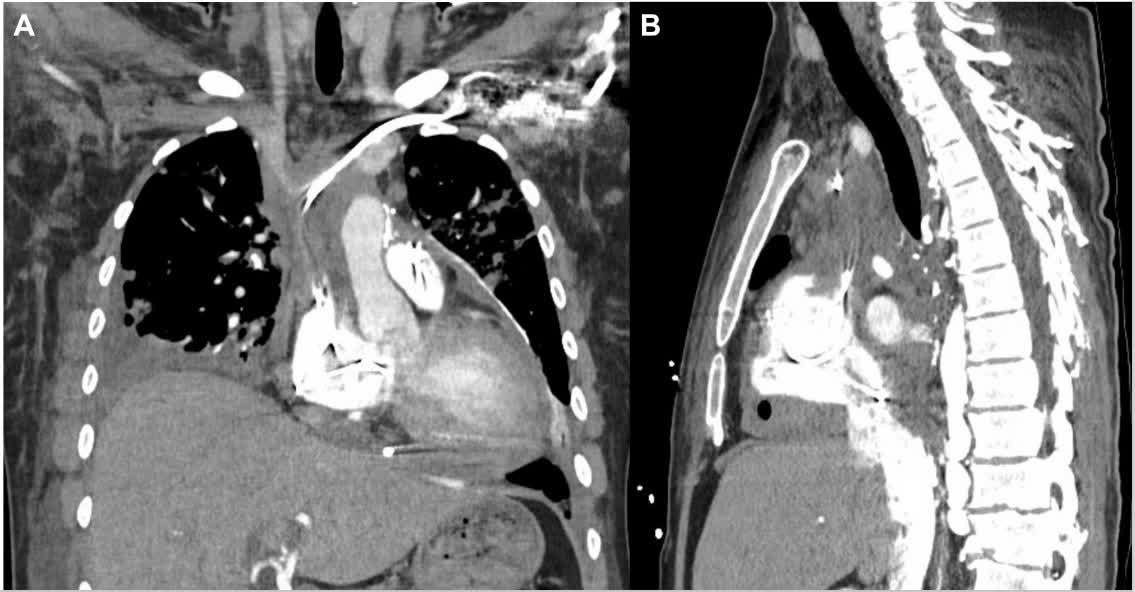

"Cardiometabolic HFpEF" should be designated "Adiposity-related HFpEF", says Milton Packer et al in Circ Heart Fail @bborlaugmd @gabrieleschiat1